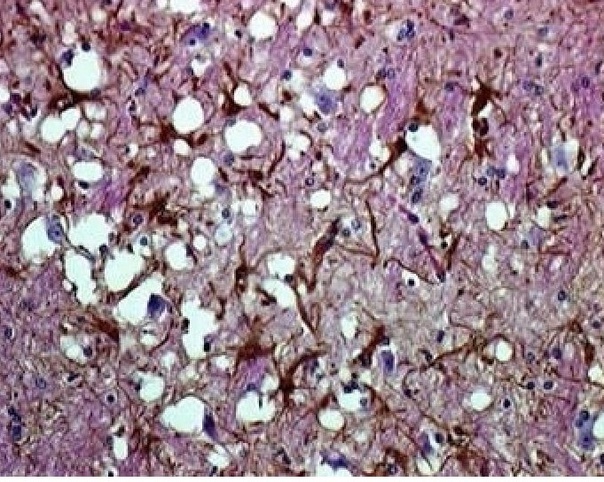

В противоположность этому инфекционный белок PrPSc накапливается в цитоплазменных везикулах, что приводит к последующему нарушению функции синапсов и развитию глубоких неврологических дефектов. Позднее PrPSc высвобождается во внеклеточное пространство и откладывается в виде амилоидных бляшек. PrPSc форма обнаружена в организме людей и животных, больных прионными заболеваниями – трансмиссивными спонгиоформными (губкообразными) энцефалопатиями.

При болезни куру патологические изменения можно наблюдать только в центральной нервной системе. Обычно они выражаются в формировании типичной губчатой энцефалопатии. В коре, подкорковых ядрах, подбугорной области и в мозжечке наблюдается вакуолизация дендритов, аксонов и тел нейронов. Вакуолизация становится настолько выраженной, что серое вещество коры большого мозга приобретает вид губки, в результате чего такое состояние обозначают как status spongiosus. Методом электронной микроскопии было выяснено, что вакуоли окружены фрагментами таких же пролиферирующих мембран. Характерный патогистологический признак при куру – выпадение нейронов.

Изменения нейронов сочетаются с гипертрофией и размножением астроцитов. При куру у человека патогистологические изменения наиболее выражены в мозжечке: появляются аморфные ШИК-положительные бляшки, содержащие амилоид, уменьшается количество грушевидных нейронов (клеток Пуркинье). Вместе с тем, при куру не удаётся обнаружить воспалительной реакции, столь характерной для многих заболеваний ЦНС, или таких характерных признаков вирусной инфекции, как образование телец включений или глиальных узлов.

Характерные для куру изменения ЦНС обнаруживаются ещё до появления клинических симптомов заболевания, что сопровождается снижением общего содержания ганглиозидов в сером веществе головного мозга на 40%. Однако сам прион не удаётся обнаружить ни в крови, ни в сыворотке, ни в моче, ни в спинномозговой жидкости. В молоке, ткани плаценты и амниотической жидкости у людей или экспериментально заражённых животных прион также не обнаруживается.

Таким образом, морфологически прионные болезни можно отнести к группе амилоидозов. Амилоидоз при прионных болезнях характеризуется отложением волокнистого амилоидного белка в головном мозгу. Образование прионных амилоидных бляшек сближает прионнные болезни с амилоидозами из группы нейродегенеративных заболеваний, таких, как, например, хорея Гентингтона. Получены убедительные доказательства того, что свойства прионных белков и амилоидов идентичны.

Тем не менее, при большом сходстве патогистологических изменений между болезнями Крейтцфельдта-Якоба, куру и скрепи имеются отличия. Так, амилоидные бляшки при болезни Кройцфельдта-Якоба наблюдаются в 9%, а при куру они встречаются в 70% случаев.